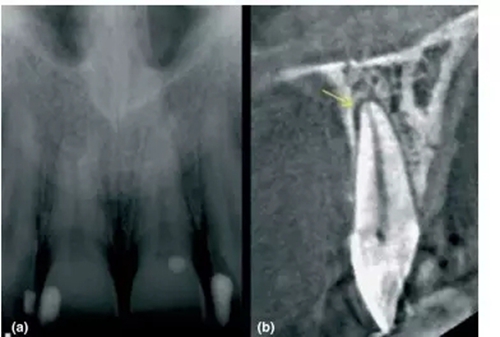

1,根尖周炎的探測(cè)

a- 11和21根尖影像無異常,但患者主訴該區(qū)有間歇的鈍痛

b-CBCT顯示21腭側(cè)有透射影,根管治療后患者癥狀消失

前文中已經(jīng)討論了能顯示在傳統(tǒng)X片上根尖周暗影,其范圍一定侵犯到皮質(zhì)骨。然而CBCT卻能精準(zhǔn)探測(cè)只局限于松質(zhì)骨中的病損,讓臨床醫(yī)生能早診斷、早處理,提高現(xiàn)代牙體牙髓治療的成功率。